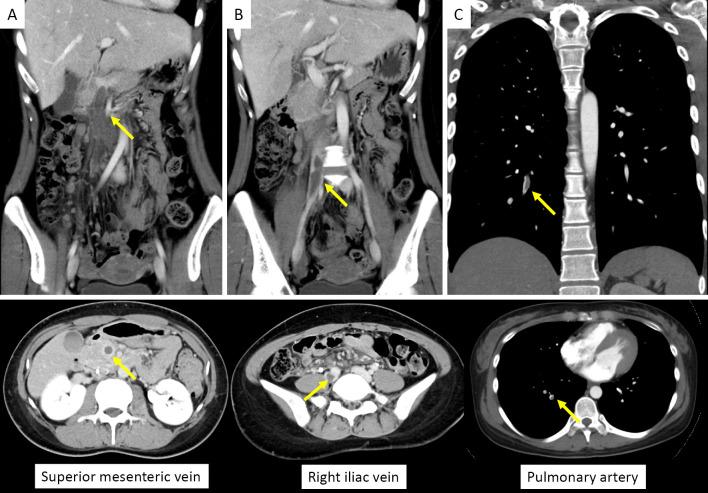

Superior mesenteric venous thrombosis (SMVT), which results from various etiologies, including coagulation disorders, can be diagnosed early using advanced imaging technology. However, few reports have described the nonsurgical treatment of acute peritonitis caused by SMVT. We encountered a young woman whose history included abdominal pain and daily oral contraceptives and who presented with acute peritonitis caused by SMVT. We administered nonsurgical treatment that included thrombolysis and anticoagulation for the peritonitis (without mesenteric ischemia as confirmed by contrast-enhanced computed tomography). In addition, we showed the importance of investigating persistent risk factors for thromboembolism in young patients to determine the duration of anticoagulation.

肠系膜上静脉血栓形成(SMVT)可由多种病因引起,包括凝血障碍等,可通过先进的影像学技术早期诊断。然而,很少有报道描述 SMVT 引起的急性腹膜炎的非手术治疗方法。我们遇到一位年轻女性,既往有腹痛病史,每日口服避孕药,因 SMVT 引起急性腹膜炎。我们对其进行了非手术治疗,包括针对腹膜炎的溶栓和抗凝治疗(增强 CT 未发现肠系膜缺血)。此外,我们还强调了在年轻患者中调查持续性血栓栓塞风险因素以确定抗凝时间的重要性。